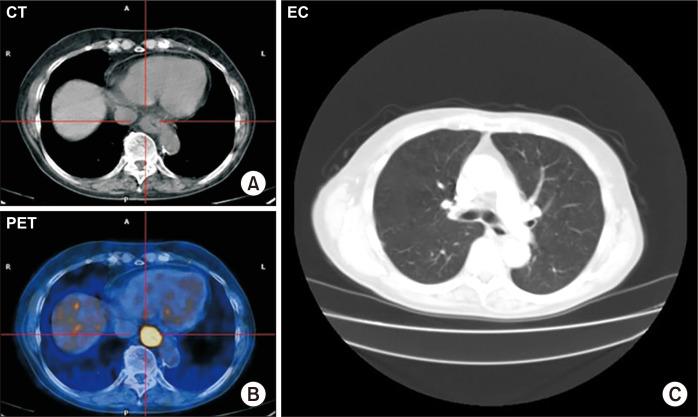

Tracheobronchial injury (TBI) is an uncommon but potentially fatal event. Iatrogenic lesions during bronchoscopy, endotracheal intubation, or thoracic surgery are considered the most common causes of TBI. When TBI is detected during surgery, concomitant surgical treatment is recommended. Herein we present a case of successful robotic primary repair of iatrogenic tracheal and left bronchial branch tears during a robot-assisted hybrid 3-stage esophagectomy after neoadjuvant chemoradiotherapy. A robotic approach can facilitate the repair of this injury while reducing both the potential risk of conversion to open surgery and the associated increased risk of postoperative respiratory complications.